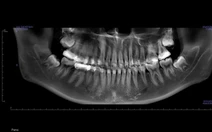

Mòn răng là sự mất chất cấu trúc răng (men, ngà) không do sâu răng, xảy ra do các yếu tố cơ học, hóa học hoặc sinh lý. Quá trình này thường diễn ra từ từ, không gây đau ngay lập tức nên dễ bị bỏ qua cho đến khi có triệu chứng rõ ràng.

- Mòn do tiếp xúc: Do răng trên và răng dưới cọ xát nhau, thường gặp ở người có thói quen nghiến răng hoặc cắn chặt răng khi ngủ. Các trường hợp có mòn răng nhiều thường có tình trạng loạn năng khớp thái dương hàm kèm theo.

- Mòn do hóa học: Hiện tượng mất men răng do axit từ thức ăn, đồ uống hoặc axit nội sinh do trào ngược dạ dày. Các nước uống có gas, có độ pH thấp nếu lạm dụng dùng nhiều có nguy cơ gây mòn răng cao.

- Bề mặt răng bị phẳng, mờ đục hoặc xuất hiện vết lõm nhỏ.

- Rìa cắn của răng cửa bị mẻ hoặc mòn ngắn lại.

- Ngà răng lộ ra, có màu vàng nhạt hoặc nâu.

- Có thể thấy vết khía ở cổ răng gần lợi.